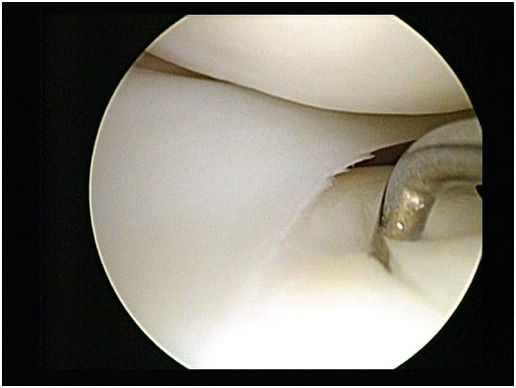

29 éves pályám során közel ezer térdprotézist és több mint kétezer csípőprotézist ültettem be. Az utóbbi években egyre több, nagy műszer igényű, összetett protézis revíziós műtétet végzek.

Fő érdeklődési köröm a biomechanika, műszerfejlesztés, új műtéti technikák kidolgozása és a nagyízületi endoprotetika.